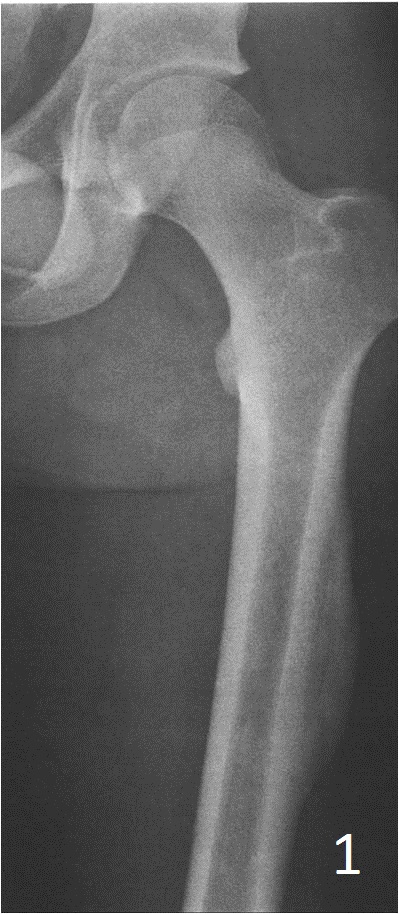

Plain Radiograph

• Periosteal reaction, with thing calcification in the periphery of the lesion (Fig. 1)

• As matures see zonal phenomenon with mature bone at periphery and immature center similar to medullary canal.